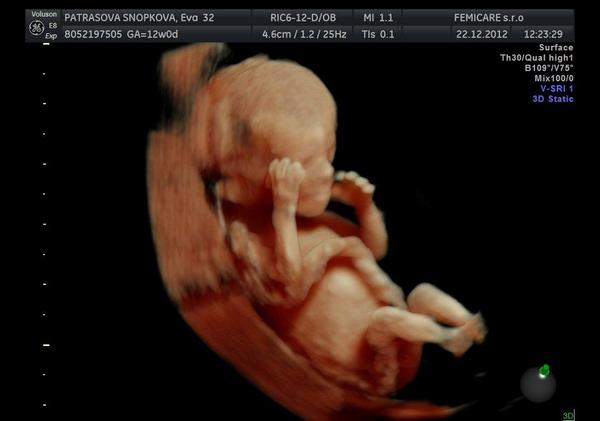

k kocky dodatocne prajem krasne sviatky boli aj krasne // vianoce @kikaneu tak gratulujem a pridavam foto nasho chlapceka

@michaelamia1902 krásne bábätko, gratulujem 😵 vidím tam tie jeho rozmery, že do 5 cm, a vyzerá ako veľký 🙂